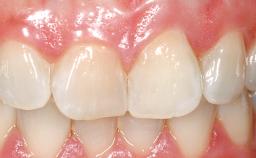

Immediate Flapless Placement of an Implant in a Maxillary Left Central Incisor Site

A 42-year-old female patient was referred to our clinic at the School of Dentistry of the University of São Paulo in November 2004, presenting a deficient restoration in the upper left central incisor. The clinical examination revealed no gingival retraction or any signs of gingival inflammation and, therefore, previous periodontal treatment was not considered. The patient presented a high lip line at full smile and a thin tissue biotype. This combination characterized a high-risk situation from an anatomic point of view, which required careful preoperative planning and cautious surgical execution.